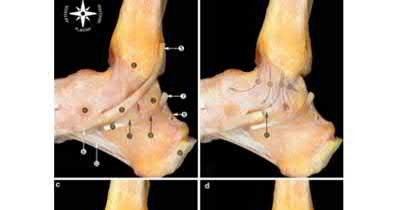

The safe zone for tibial nail placement as seen on radiographs is just medial to the lateral tibial spine on the anteroposterior radiograph and immediately adjacent and anterior to the articular surface as visualized on the lateral radiograph.

Tornetta et al specifically located the safe zone for nail entry in a study using fresh frozen cadaver knees. The authors found that the safe zone for nail placement is located 9.1+/-5 millimeters lateral to the midline of the plateau and three millimeters lateral to the center of the tibial tubercle. The width of the safe zone averaged 22.9 millimeters and was as narrow as 12.6 millimeters.

The starting point of the of the nail can be best viewed on the lateral knee radiograph, an example of which is shown in Illustration A. Illustration B shows the "sweet spot" for nail insertion as defined by Tornetta.